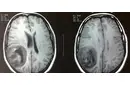

Beyin Dokusunun Sağlık Üzerindeki Etkileri Beyin dokusunun sağlıklı bir şekilde işlev görmesi, genel sağlık üzerinde büyük etkiye sahiptir. Beyin dokusundaki hasar veya bozulmalar, birçok nörolojik hastalığın temelini oluşturur. Öne çıkan sağlık sorunları arasında: